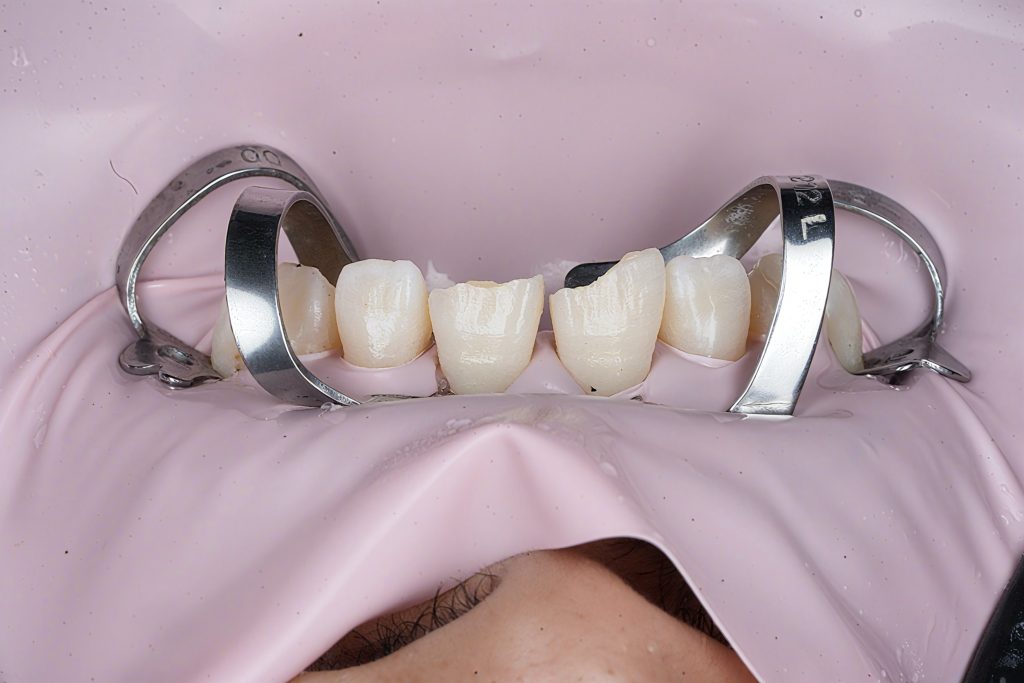

2. Rubber Dam Isolation

A pink dam clamp setup was used to stabilise the working field, protect the gingiva, and maintain clean bonding conditions.